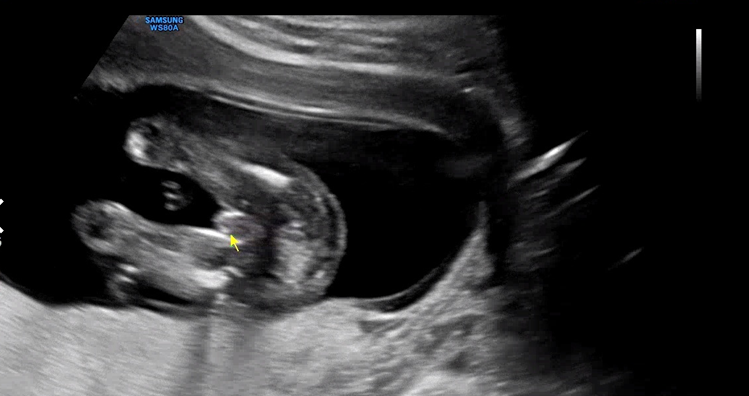

우리 아기는 고추. 16주부터는 아들, 딸 성별을 초음파로 알 수 있는데 20주가 되도록 언급이 없는 병원도 있다고 들었다. 나도 그냥 자연스레 알겠지 하고 있었는데 너무나 아무렇지 않게 아들이네요~ 하고 알려주셨다. 남편은 딸을 원했는데 아무리 봐도 초음파 움직임이 남편 느낌이라 뭔가 예전부터 아들 같긴 했었다.

부정할 수 없는 아들 포스. 짜리 몽땅한 다리도 너무 귀엽다.

꼬물꼬물 움직이는 아기를 관찰하다 발가락도 이렇게 예쁘게 생긴 걸 보여주셨다.

손을 입에 대었다 주먹을 꽉 쥐었다 열심히 움직이는 우리 아기. 아기가 잘 움직이는 건 너무 좋은 증상이라도 원장님이 말씀해주셨다. 16주부터는 대략적인 태아의 체중을 측정할 수 있는데 155g으로 무럭무럭 자라고 있다. 임신이라고 크게 뭘 하지 않는데도 혼자서 너무 잘 자라주고 있어서 기특하다.